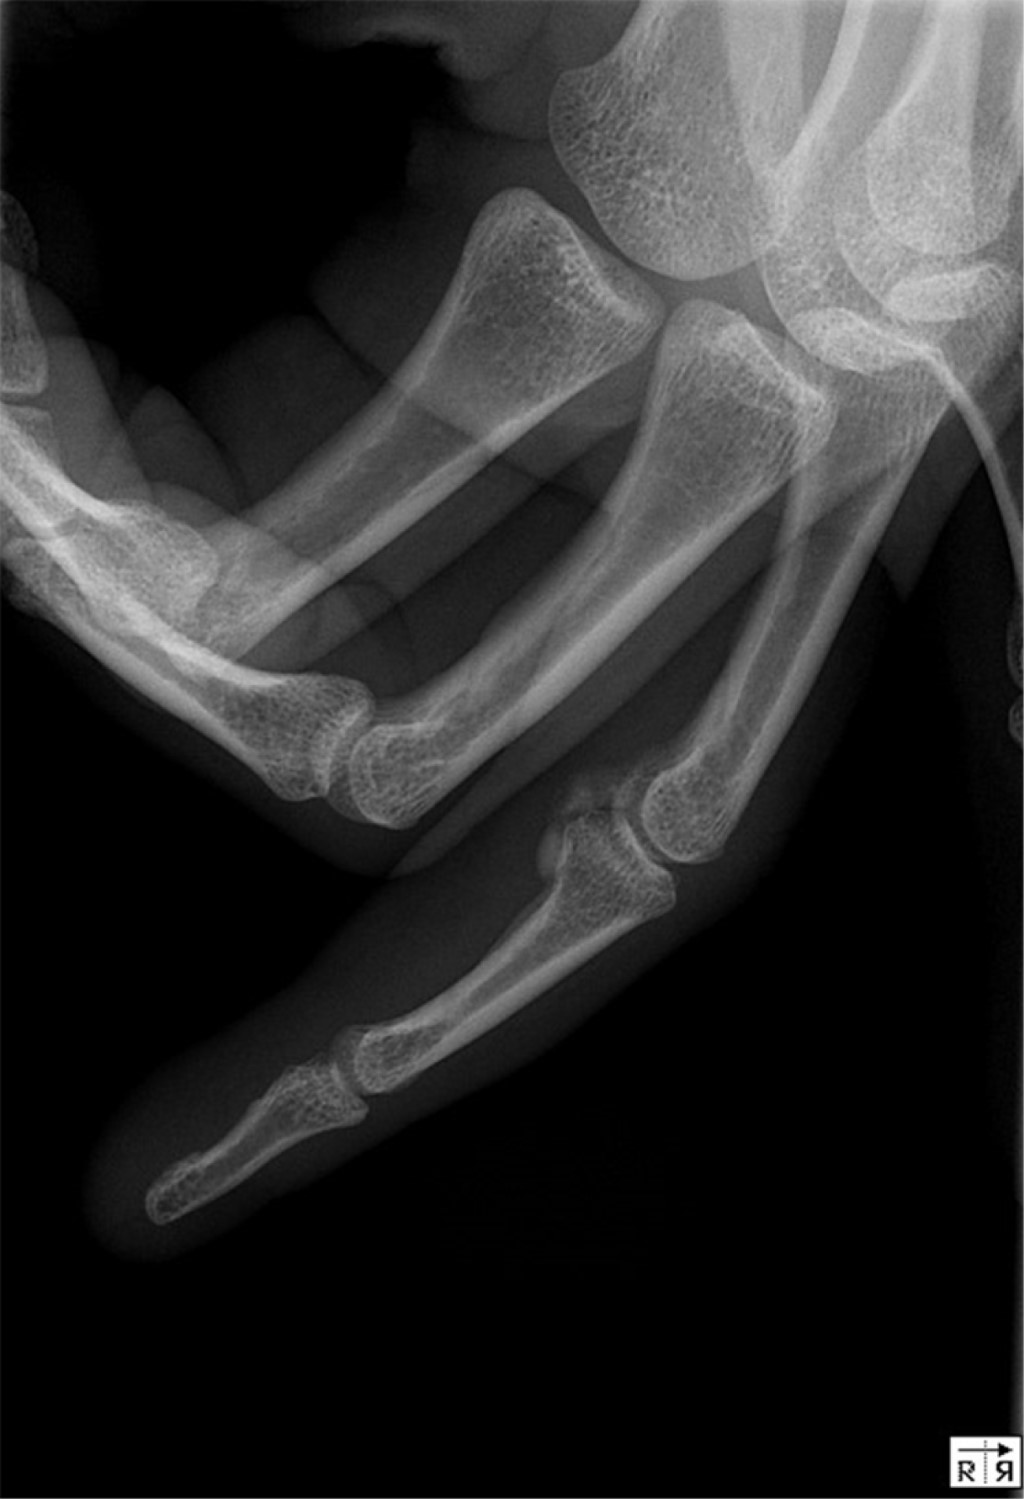

A 25-year-old right-hand dominant black woman, who works as a waitress, was observed in the emergency room (ER) after an acute trauma of the fourth finger of the right hand. The patient reported no relevant medical history. She experienced pain on palpation of the volar aspect of the PIP joint, where a soft tissue mass was present. On the radiograph of the hand, an abnormal lesion compatible with a calcification could be seen on the volar side of the PIP joint of the fourth finger; there was no periosteal reaction, evidence of joint space narrowing or cortical lesion, and the calcification was separated from the bone (Figure 1). The patient was discharged with recommendations for analgesia and syndactyly.

The patient returned to the ER after two days referring worsening of the pain at the PIP joint. This time, the range of motion was fairly impaired due to pain and there was visible edema. Tenderness along the flexor tendon sheath was not present. The plain radiograph was similar to the previous one (Figure 1). The ultrasound confirmed a calcification of the volar plate, and blood tests were normal. After the evaluation, an infection of the flexor sheath seemed unlikely and the diagnosis of an ACP of the PIP joint was made. The patient was medicated with a corticoid along with painkillers.